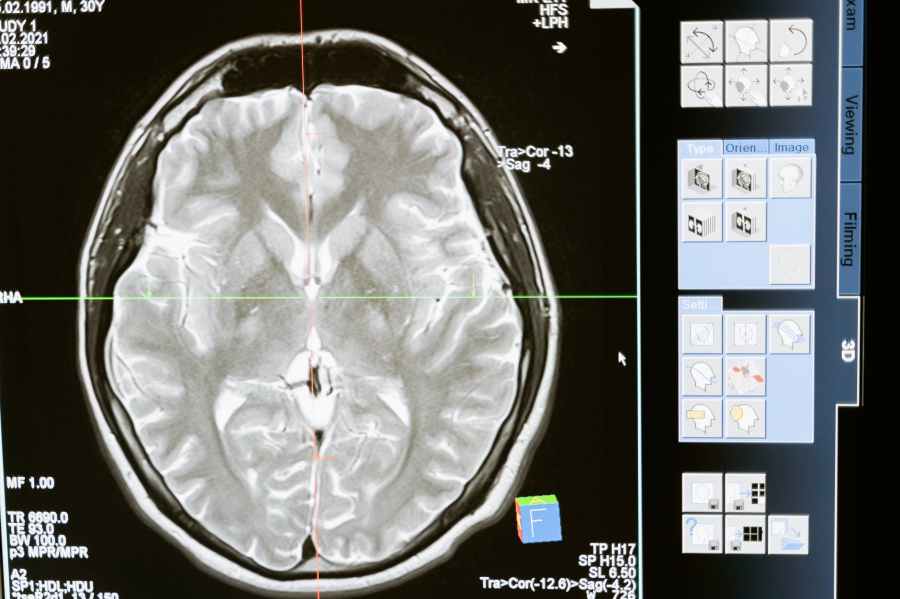

Dies hier wird Ihr Gehirn verändern!

Die neuronale Plastizität ist die Grundlage für Lernen und Entwicklung.Ich möchte Ihnen gerne einen wundervollen Vortrag vorstellen, der sowohl kurzweilig als auch informativ ist. In diesem Sinne: Quod erat demonstrandum. https://www.youtube.com/watch?v=LNHBMFCzznE